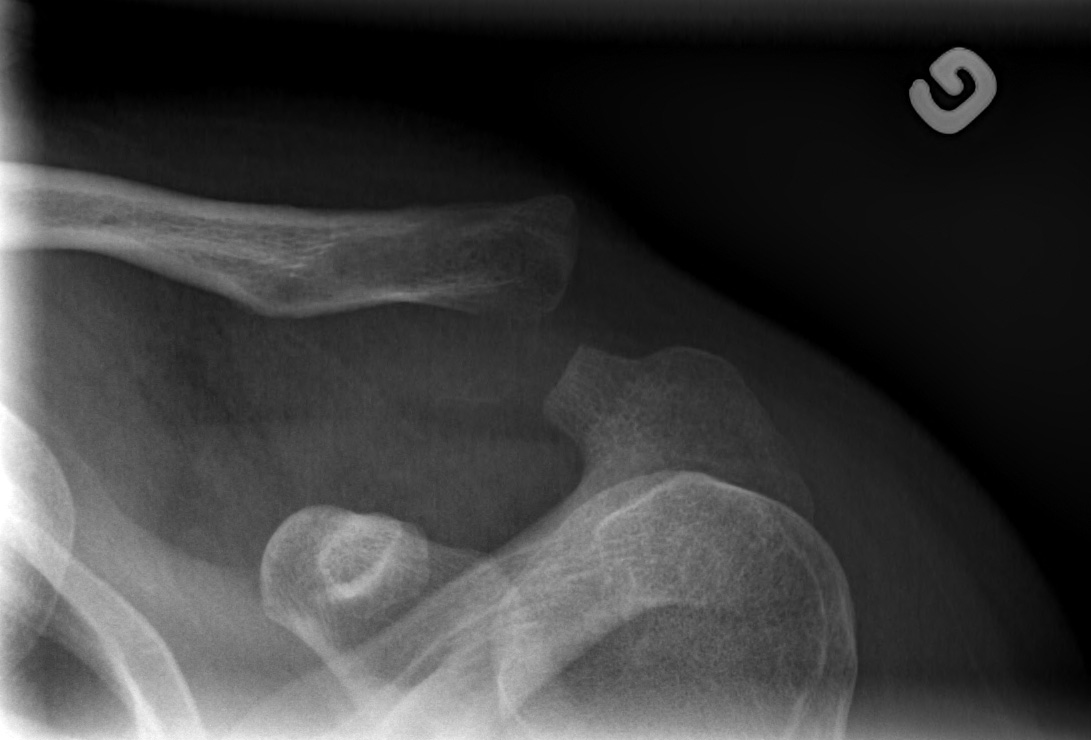

27-year-old male:

Left shoulder pain following a direct fall on the shoulder.

Acromioclavicular luxation

Bone misalignment

The left clavicule is displaced superiorly with increased acromioclavicular and coracoclavicular distance relative to the right side.

Displacement measurement

Superior displacement of the left clavicle with a coracoclavicular distance of 32 mm compared to 13 mm on the right side (146% displacement). This is thus a grade 5 acromioclavicular joint dislocation.